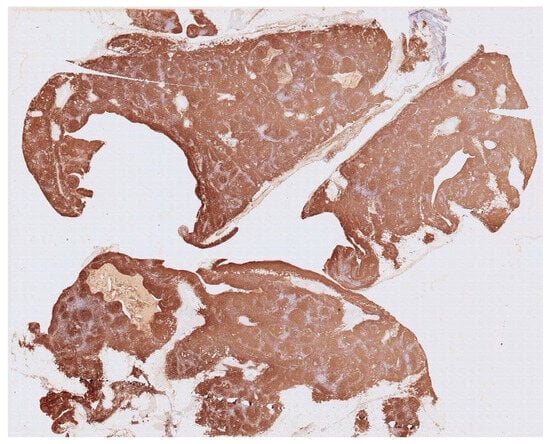

Histology showed an MTC lined by cubic epithelium and rich in lymphoid tissue, organized in germinal centers (CD10+, BCL6+, BCL2−, CD21+, CD23+), and a mantel zone (CD79A+, BCL2+), the interfollicular region represented by T-cell (CD3+), and occasional Hassall’s Corpuscles (Figure 2, Figure 3 and Figure 4).

Figure 3. Immunohistochemistry for CD20 shows the nodular architecture of the lymphoid tissue with T cell (CD20-negative) in the internodular zone (light areas between brown zones).